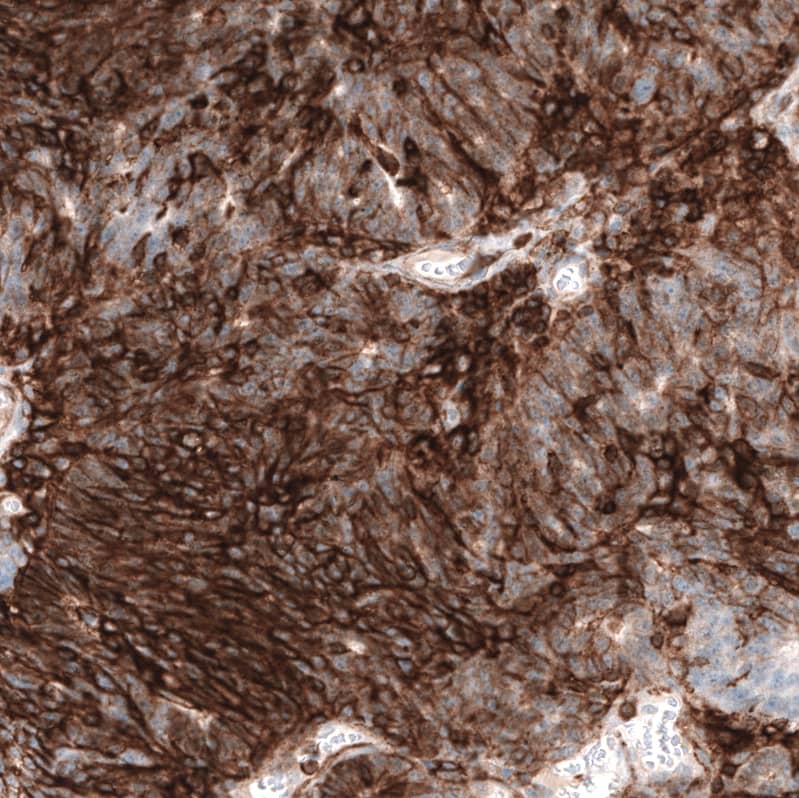

Staining of human cervical cancer shows strong membranous positivity in tumor cells.